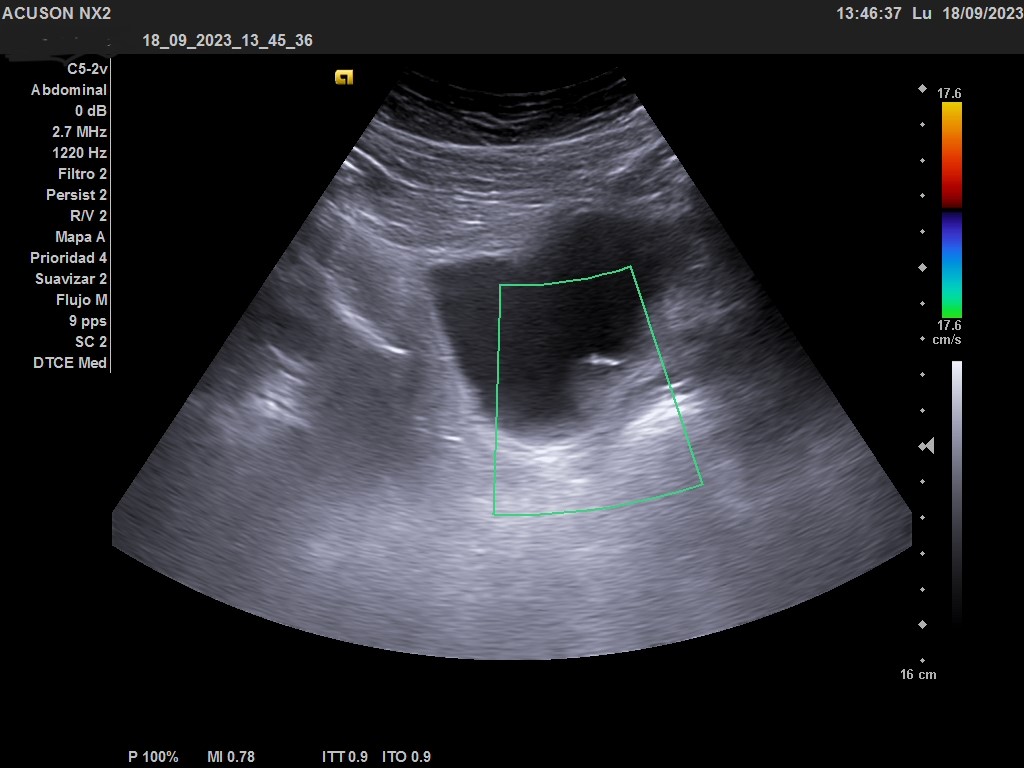

Ecografía clínica urológica: vejiga moderadamente replecionada. Se visualiza en pared posterior imagen hiperecogénica que no capta al Doppler color, de características sospechosas de malignidad. Riñones sin alteraciones en parénquima ni signos de hidronefrosis.

En la ecografía urológica reglada ambos riñones son de tamaño normal y parénquima conservado. La vejiga está replecionada, pero se identifica un engrosamiento nodular de 26 x 15 mm en la pared inferolateral izquierda, próxima al meato. Próstata de pequeño tamaño con un volumen de 7 cc.